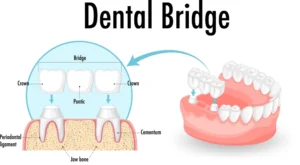

تركيبات الاسنان:

من ناحية أخرى ، كانت تركيبات الأسنان خيارًا شائعًا لأولئك الذين يبحثون عن حل غير جراحي وبأسعار معقولة للأسنان المفقودة. وهي عبارة عن مجموعة من الأسنان واللثة الاصطناعية القابلة للإزالة والتي يتم تخصيصها لتناسب فم المريض.